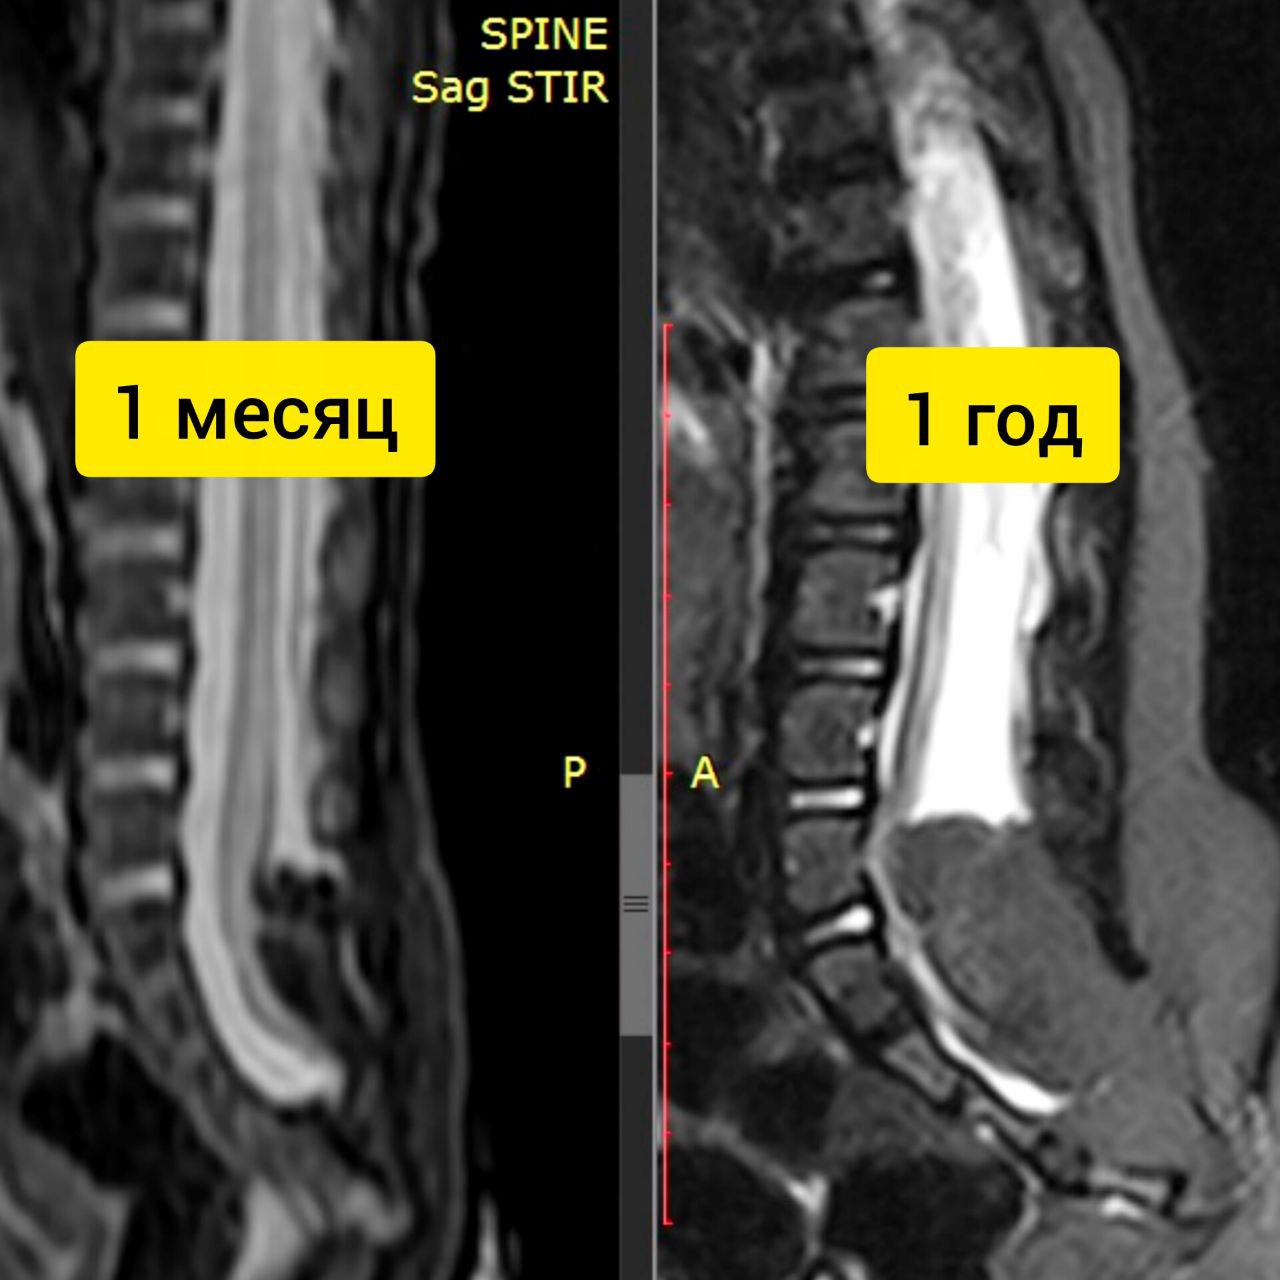

Проблемой под названием «синдром фиксированного спинного мозга» я занимаюсь предметно больше 15 лет, за это время написано немало научных статей, предложено несколько изобретений, защищена целая диссертация.

Однако, сама болезнь не перестает преподносить сюрпризы. Действительно, нередко этот синдром не является проявлением привычных форм Spina Bifida (пороков развития спинного мозга), а входит в состав генетических синдромальных (Куррарино, VACTERL, KBG), системных (EDS) и метаболических патологий.

При этом эффекты, оказываемые проведенной у таких пациентов операцией, зачастую распространяются далеко за пределы каудальных отделов спинного мозга и превосходят таковые при типичных формах спинальных дизрафий, что требует анализа и дальнейшего изучения.